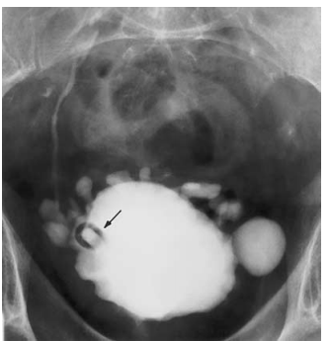

focal urethritis cystica

multiple small 2-5 mm smooth-walled rounded lucent filling defects projecting into the lumen

condition is seen in diabetics with recurrent urinary tract infections. As such, it is most frequently seen in older patients and is more common in women.